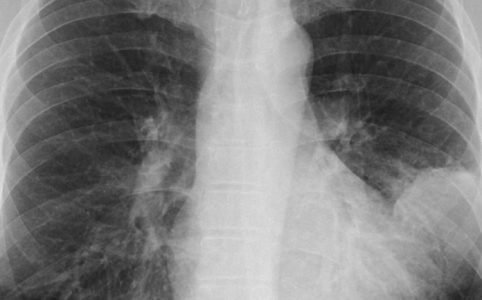

Zur Diagnose werden zuerst Anamnese, Inspektion und Auskultation (Abhorchen von Lunge und Herz) durchgeführt. Blutbild und Speichel werden auf Erreger hin untersucht. Das Röntgenbild zeigt einen „angeschwollenen“ Lungenbereich – hier in der Röntgenaufnahme links:

Abb1.: Röntgenaufnahme einer Lunge – Diagnose Lungenentzündung; zum Vergrößern auf das Bild klicken.